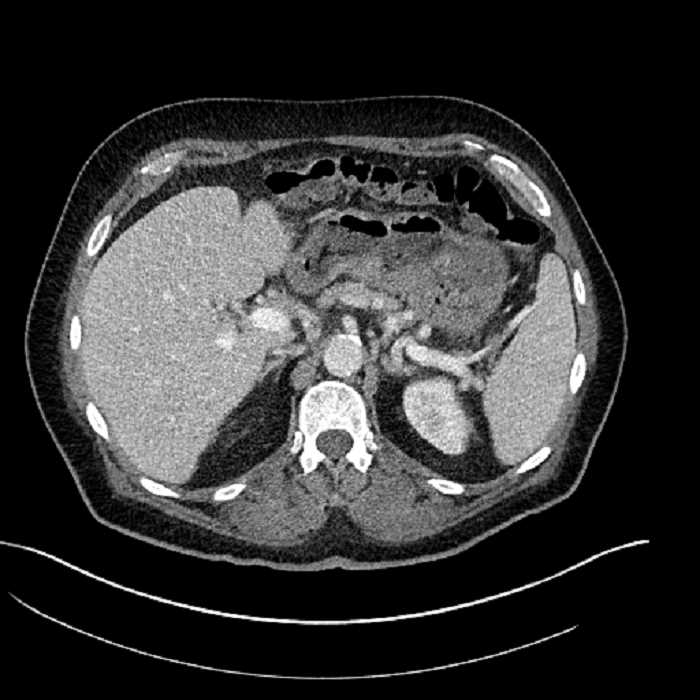

• Large fluid density structure in hepatic segments 7 and 8 measuring 10 x 7 x 7 cm with internal septation and circumferential ill-defined low density compatible with edema

• Peripherally enhancing subcapsular collections along the anterior margin of the left hepatic lobe measuring 3 x 1 cm and 2 x 1 cm

• Clearly marginated fluid density structure in segment 7 and several other scattered tiny hypodensities, which likely represent cysts

Acute sigmoid diverticulitis complicated by a small contained perforation and a large abscess in the right hepatic lobe. Additional small subcapsular abscesses along the anterior margin of the left hepatic lobe.

• The classic CT imaging appearance is a double target sign with internal low density surrounded by an internal enhancing rim (capsule) and a low density external rim (edema)

Hepatic abscess showing the double target sign with low density internally surrounded by a thin inner enhancing rim (red arrow) and ill-defined outer low density rim (yellow arrow). Blue arrow indicates an internal septation. Red arrows: additional smaller subcapsular abscesses. Red arrow: focal contained perforation associated with diverticulitis.